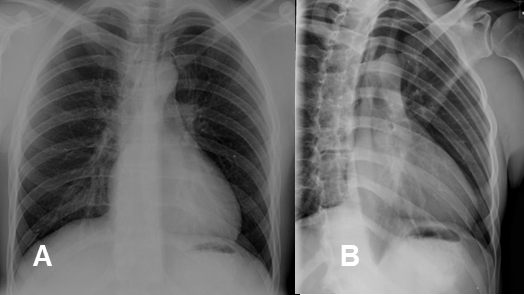

La reja costal se valora con proyecciones PA y oblicua. (Fig 5).

Fig 5. Costillas normales.

A: Rx PA y B: Rx oblicua. En la proyección oblicua se aprecian mejor las costillas, porque disminuye la superposición de estructuras.